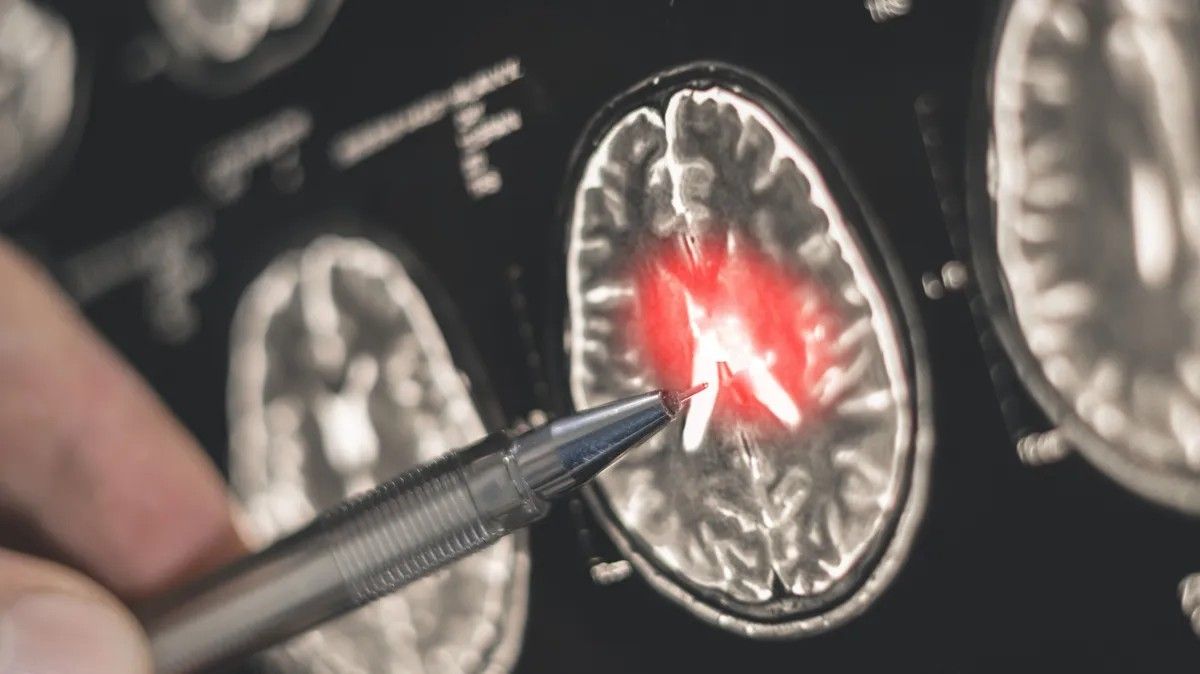

Kezdetben az orvosok nem találtak semmit, de októberben egy CT-vizsgálat során folyadék jelenlétét észlelték az agyában. Ezt követően azonnali műtétre volt szükség, amely október 17-én történt meg. A beavatkozás után Jessica nehéz időszakon ment keresztül, de az orvosok fantasztikus munkát végeztek, hogy eljuttassák őt a felépülés útjára.